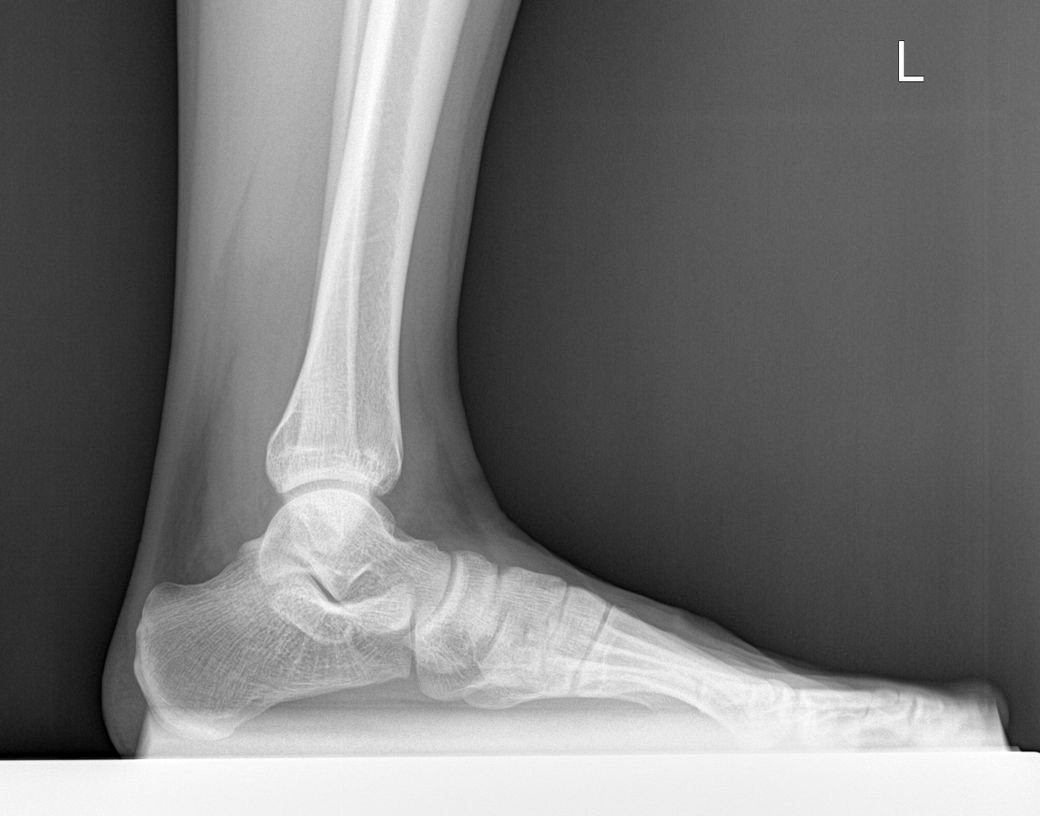

평발 측정을 위해 거골 - 제1중족골 각도가 궁금합니다.

• 1번 째 사진

우측보단 좌측발이 좀더 meary angle이 나올것으로 보이나 전체적으로 심하지 않은 편입니다.